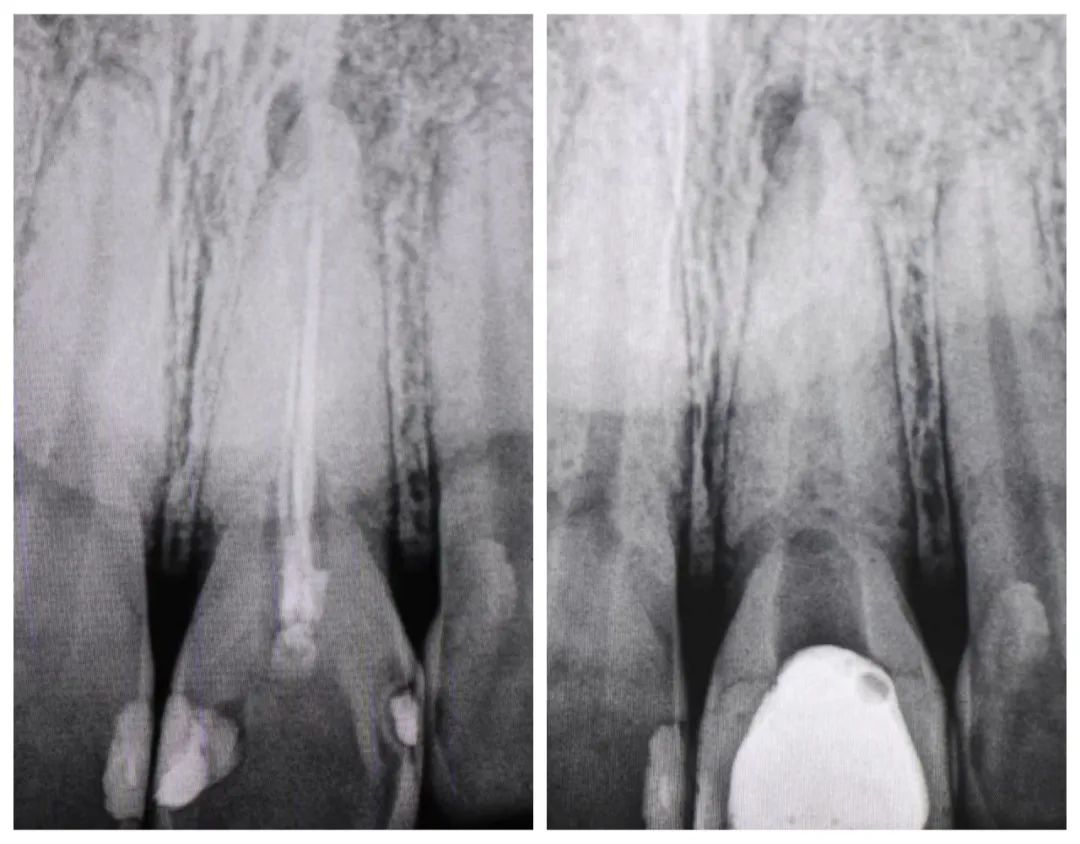

陈某,28岁,3年前因左上前牙因龋坏严重在外口腔门诊就诊后被告知龋坏严重需“根管治疗”,治疗后行树脂充填修复,期间无不适,近1年来发现患牙变色严重、未及时处理,愈发严重,现前来我院口腔科就诊。经完善口腔检查后发现21号牙着色严重,舌侧窝、近远中边缘嵴均有牙色充填体,打开后发现牙体髓腔内有大量腐质和污染的充填物;X线根尖片显示近远中、舌侧窝有充填体洞底暗影明显,根管内充填物不密实和不到位、根尖区阴影4×4mm。诊断为:21慢性根尖周炎、内源性着色牙、继发龋、牙体缺损。治疗计划:①21根管再治疗+内漂白术+纤维桩+复合树脂充填;②21根管再治疗+内漂白术+纤维桩树脂核+全瓷冠修复;③21根管再治疗+内漂白术+纤维桩树脂核+瓷贴面修复。知情同意后患者先选择方案①。经过6次显微诊疗后着色牙里里外外都变动非常干净,颜色也逐渐恢复到与邻牙接近,经5个月的随访根尖区的炎症也基本消退。

术前根尖片

术后根尖片